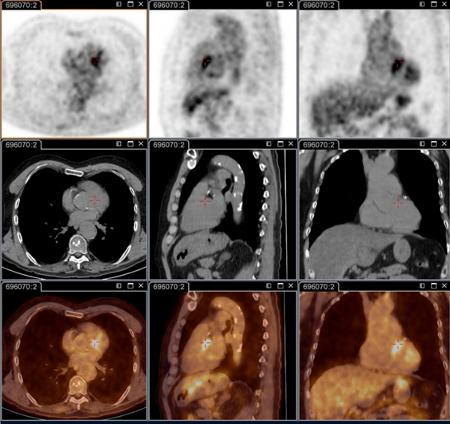

18F-ფთორდეზოქსიგლუკოზით (FDG) PET/CT სკანირება

ტესტი

კრიტიკული მნიშვნელობისაა პერსისტენტული ფოკალური ინფექციების იდენტიფიცირებისათვის.[78]

კვლევის ამ მეთოდით შესაძლებელია ენდოკარდიტის, სისხლძარღვოვანი ინფექციის, ლიმფადენიტის, ძვალსახსროვანი ინფექციების გარჩევა. ამ მიდგომის გარეშე ჩამოთვლილი მდგომარეობების იდენტიფიცირება შეუძლებელია.

ამჟამად აღნიშნული კვლევა სტანდარტული ანატომიური კვლევის მეთოდია პერსისტენტული სიმპტომების და/ან პერსისტენტულად მომატებული სეროლოგიური მაჩვენებლების და/ან სისხლის ან შრატის დადებითი პჯრ-ის მქონე პაციენტებში, ან ნებისმიერ შემთხვევაში როცა კლინიკური გამოვლინება არ შეესაბამება პირველად ინფექციას.[3]

კონკრეტულად რეკომენდებულია შემდეგი პაციენტებისთვის: მწვავე Q ცხელება პერსისტენტული I ფაზის IgG ≥1:800 და/ან ვლინდება ცუდი კლინიკური განვითარება; მწვავე Q ცხელება სისხლძარღვის გრაფტის ან ანევრიზმის ანამნეზით; ან აუხსნელი (I ფაზის IgG ≥1:800) სეროლოგიით ან პერსისტენტულ ინფექციაზე კლინიკური ეჭვის დროს.

ასევე გამოსადეგია ინფექციის იდენტიფიცირება პაციენტებში, რომელთაც აღენიშნებათ სისხლძარღვის პროთეზი და/ან ანევრიზმა. საჭიროა გადაწყვეტილების მიღება, თუ რომელ პაციენტს ესაჭიროება ქირურგია ინფიცირებული სისხლძარღვოვანი ქსოვილების ამოსაკვეთად.[Figure caption and citation for the preceding image starts]: Q ცხელების ენდოკარდიტი, PET სკანირება: 18F-ფთორდეზოქსიგლუკოზა PET/CT. პაციენტი უსიმპტომოა, ანამნეზში აქვს სარქველის პრობლემა, მომატებულია სეროლოგია. PET სკანირებით დიაგნოსტირდა აორტის ენდოკარდიტი ბუნებრივ სარქველზე, თორაკალური და წელის აორტის მიკოზური ანევრიზმებითInstitut Hospitalo-Universitaire Méditerranée Infection (პაციენტის ნებართვა აღებულია) [Citation ends].

[Figure caption and citation for the preceding image starts]: Q ცხელების აორტული მიკოზური თორაკალური ანევრიზმა - PET სკანირება: 18F-ფთორდეზოქსიგლუკოზა PET/CT. პაციენტი უსიმპტომოა, ანამნეზში აქვს სარქველის პრობლემა, მომატებულია სეროლოგია. PET სკანირებით დიაგნოსტირდა აორტის ენდოკარდიტი ბუნებრივ სარქველზე, თორაკალური და წელის აორტის მიკოზური ანევრიზმებითInstitut Hospitalo-Universitaire Méditerranée Infection (პაციენტის ნებართვა აღებულია) [Citation ends].

[Figure caption and citation for the preceding image starts]: Q ცხელების აორტული მიკოზური ანევრიზმა - PET სკანირება: 18F-ფთორდეზოქსიგლუკოზა PET/CT. პაციენტი უსიმპტომოა, ანამნეზში აქვს სარქველის პრობლემა, მომატებულია სეროლოგია. PET სკანირებით დიაგნოსტირდა აორტის ენდოკარდიტი ბუნებრივ სარქველზე, თორაკალური და წელის აორტის მიკოზური ანევრიზმებითInstitut Hospitalo-Universitaire Méditerranée Infection (პაციენტის ნებართვა აღებულია) [Citation ends].